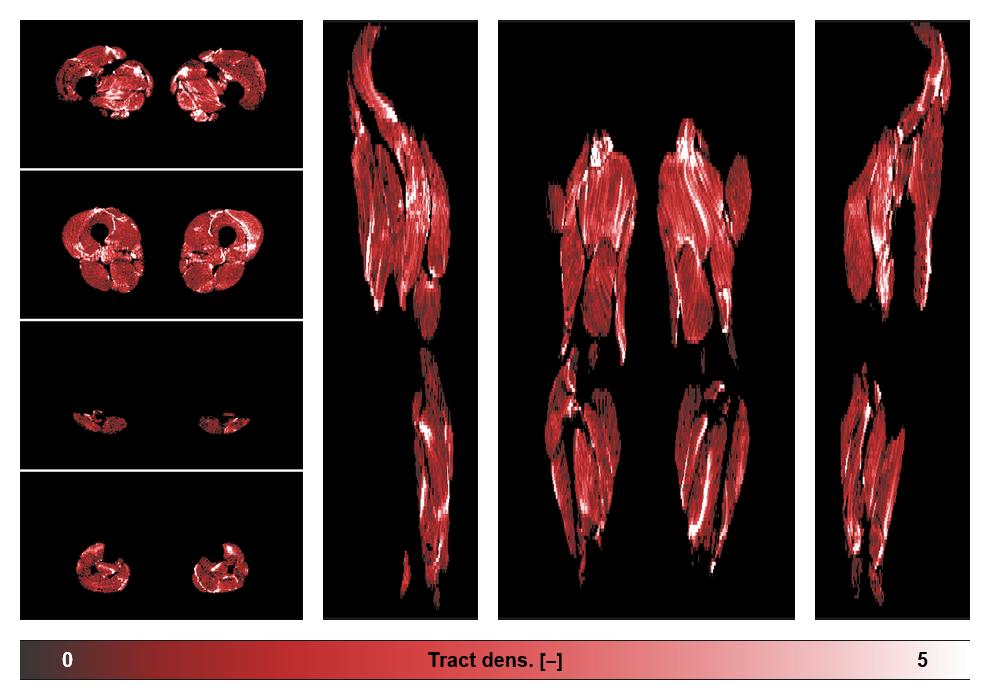

• Muscle fiber density map

Muscle fiber tract density map based on whole leg DTI based fiber tractography.